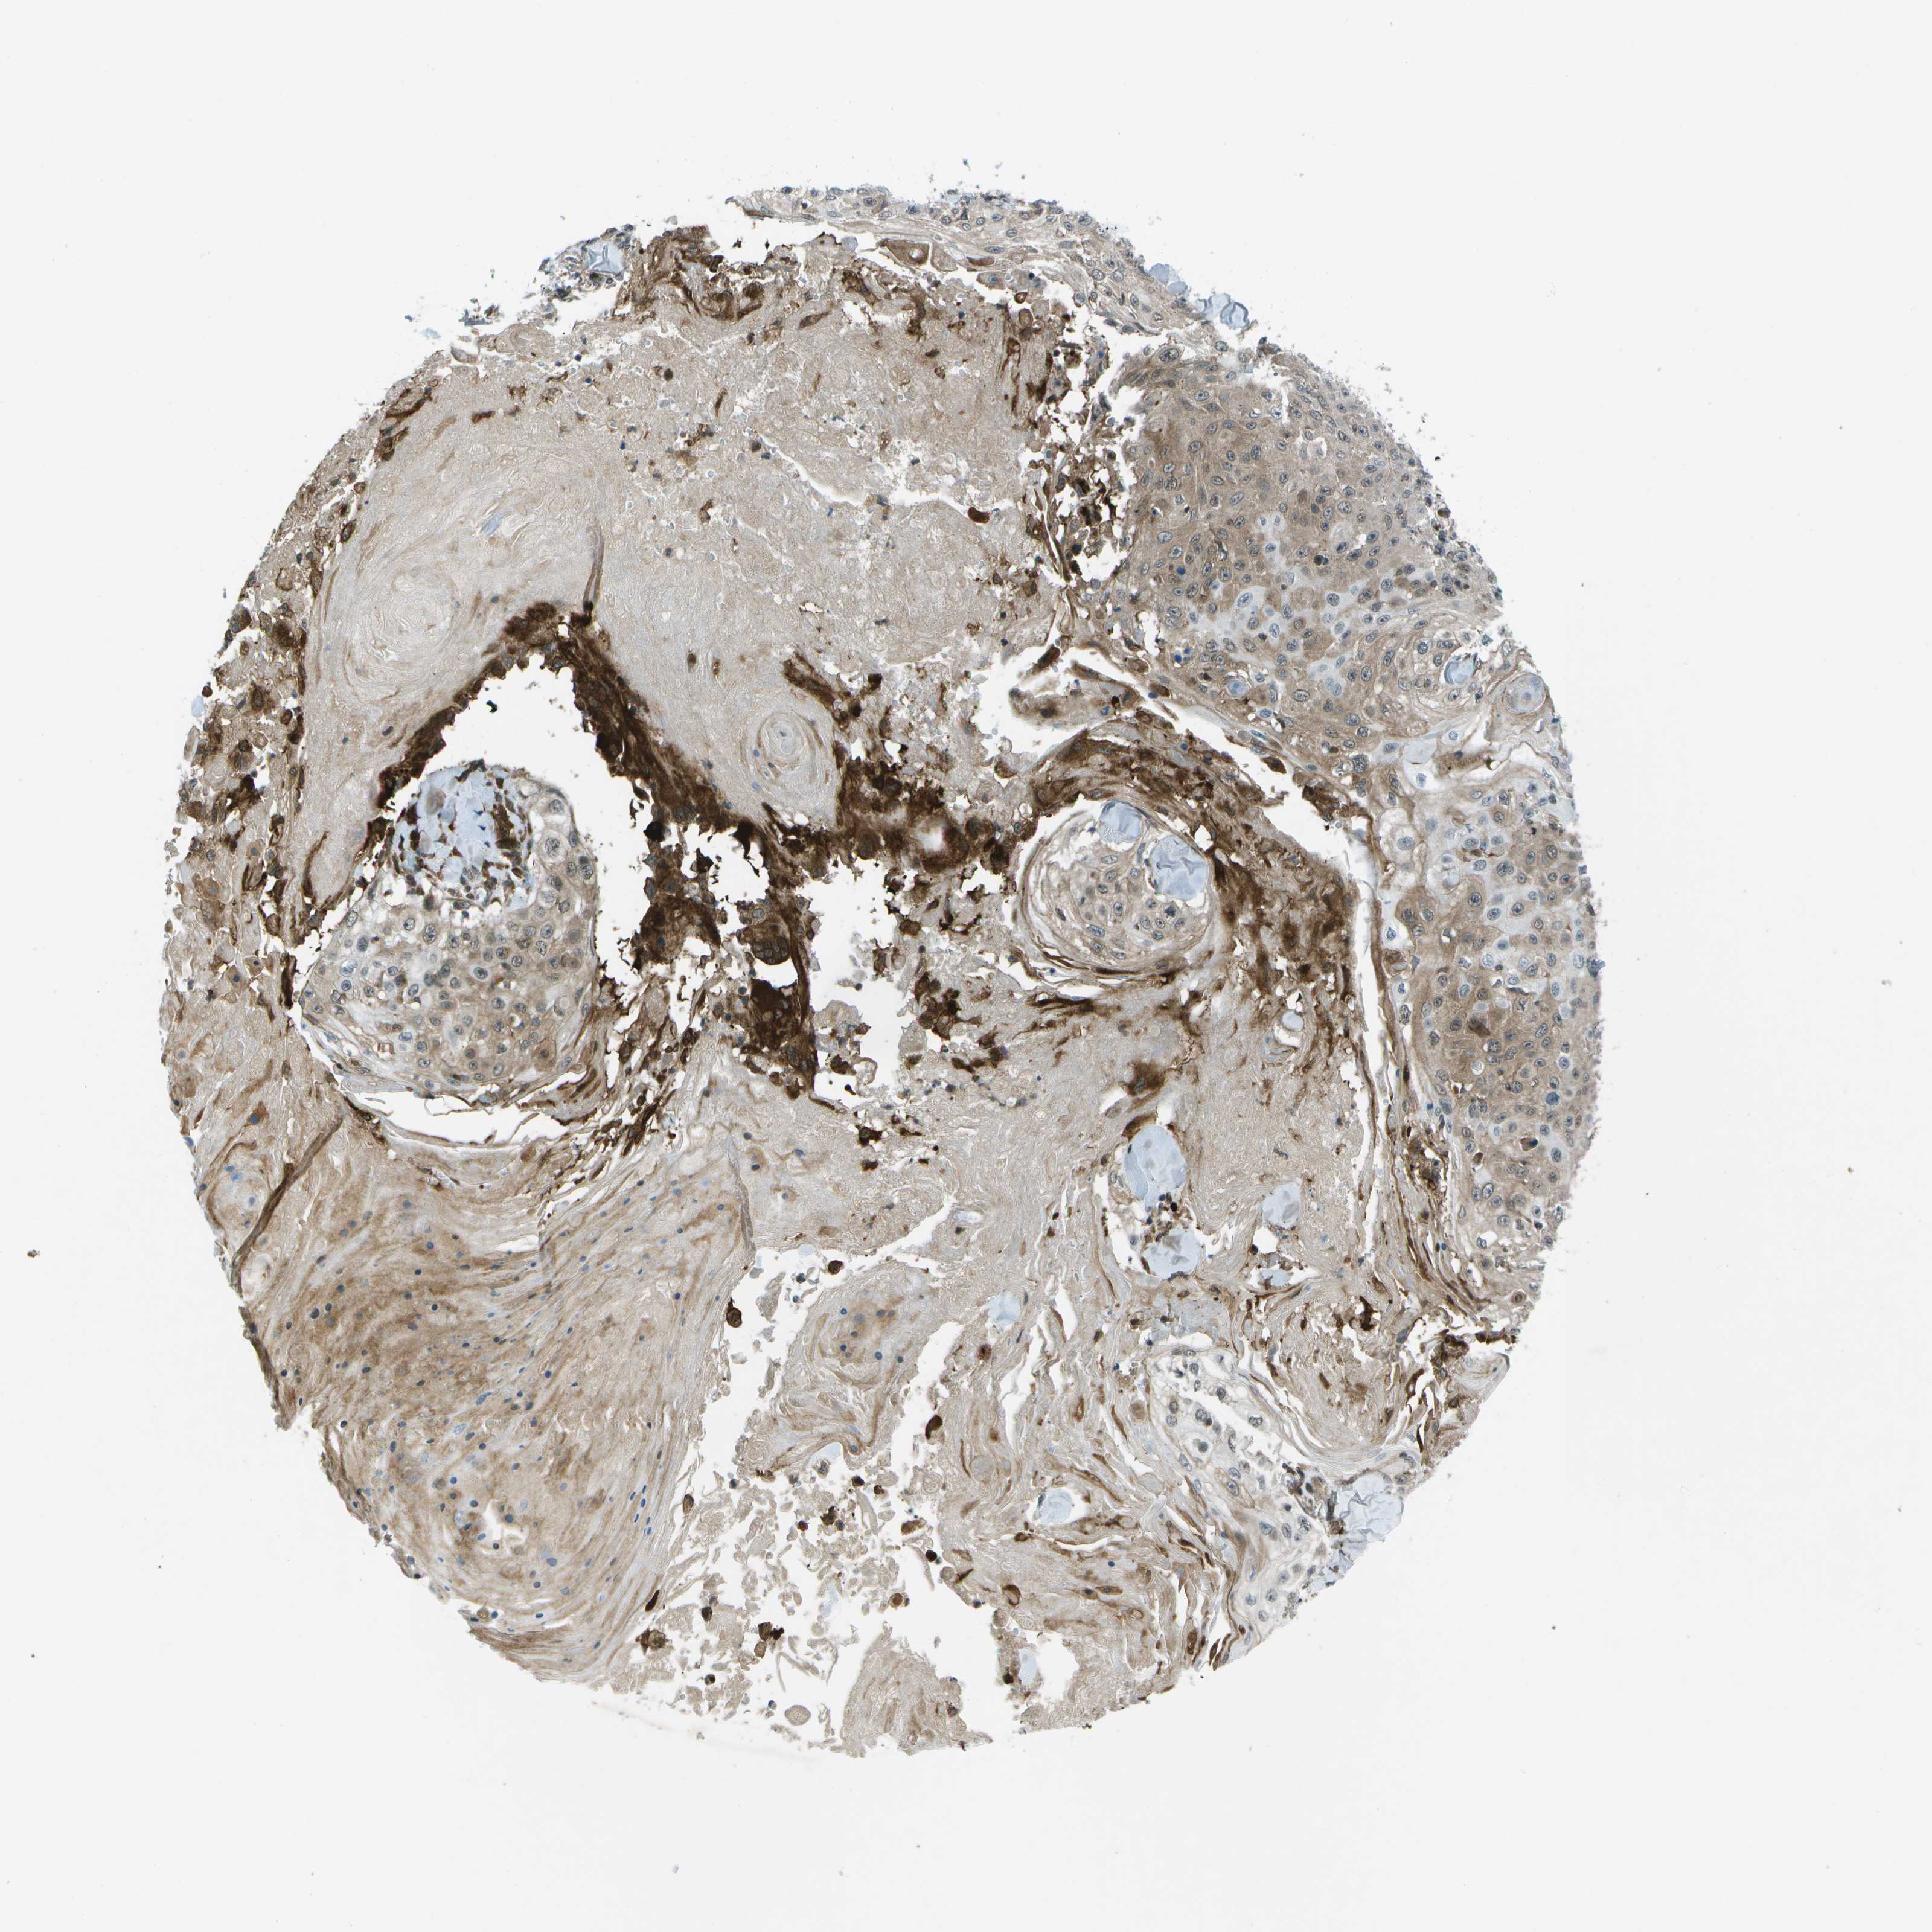

SKIN CANCER - Protein expressioni

A mouse-over function shows sample information and annotation data. Click on an image to view it in a full screen mode. Samples can be filtered based on level of antibody staining by selecting one or several of the following categories: high, medium, low and not detected. The assay and annotation is described here.

Each image is clickable and will lead to virtual microscopy that enables deeper exploration of all samples and also displays staining intensity scores, fraction scores and subcellular localization as well as patient and tissue information for each sample.

Antibody HPA016830

Staining

High

Intensity

Strong

Quantity

>75%

Location

Nuclear

Squamous cell carcinoma in situ, NOS

Squamous cell carcinoma, NOS

Squamous cell carcinoma, metastatic, NOS

Basal cell carcinoma

Adnexal tumor, benign